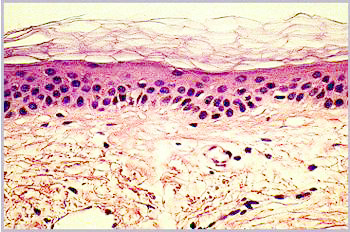

Gealterte Haut ist auf den ersten Blick durch das Auftreten von Falten, Schlaffheit und Altersflecken zu erkennen. Im histologischen Schnitt erkennt man auch einige Ursachen für diese Alterszeichen (Abbildung 1).

Abbildung 1a: Mkroskopischer Schnitt durch die Haut einer 21-Jährigen

Abbildung 1

Mikroskopische Schnitte durch die Haut von einer 21-Jährigen (a) und einer 66-Jährigen (b)

In junger Haut ist der untere Teil der Haut, die Dermis sehr regelmäßig aufgebaut. Diese klare Struktur ist im Alter gestört: Die Dermis enthält unregelmäßige Strukturen und Fehlstellen und erscheint weniger kompakt. Die nächsthöhere Schicht, die Epidermis, ist im Alter etwas dünner als in junger Haut. Viel auffälliger als diese geringe Änderung der Epidermisdicke ist aber das Verschwinden der Krümmungen der epidermalen-dermalen Grenzfläche. In gealterter Haut ist diese Grenzfläche flach, was zu einer Schwächung der Kohäsion zwischen Dermis und Epidermis führt. In der obersten Schicht schließlich, dem Stratum Corneum, sind im Mikroskop kaum Unterschiede festzustellen.